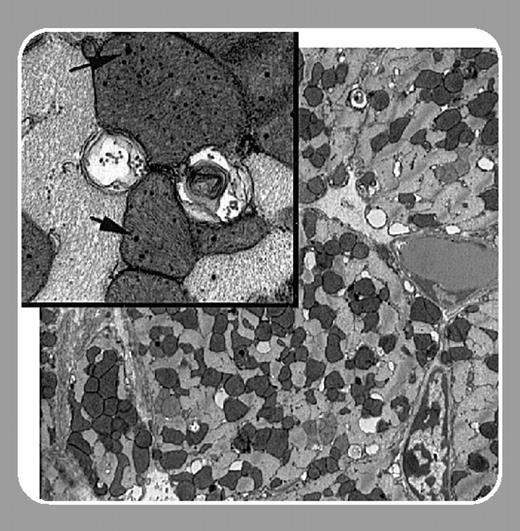

To further simulate the distribution of hemochromatosis mutations in the general population, they studied the effect of chronic administration of DOX on both heterozygous and homozygous knockout mice. Both groups of mice displayed increased mortality and excessive iron accumulation when compared with wild-type mice. Significantly, Miranda et al show that the iron accumulation results in extensive mitochondrial damage in heart tissue.FIG1

Recently, Swain et al1 reported that DOX-related cardiotoxicity and induced congestive heart failure occur at a greater frequency than was previously reported, and that patients of advanced age may be at a greater risk. As iron accumulation increases with age, this observation has profound implications when considered along with the results presented by Miranda et al. These studies warrant a closer look at the relationship between DOX cardiotoxicity and the prevalence of HFE mutations and other genetic changes that affect iron homeostasis.